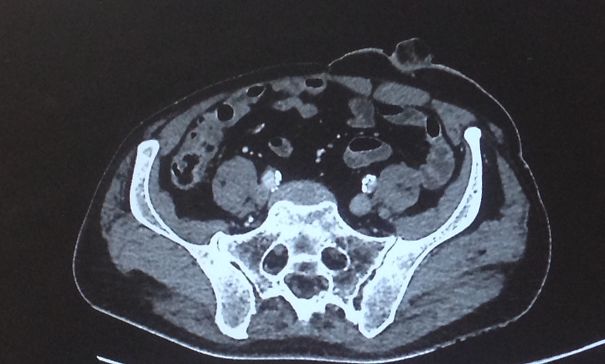

Sally From Xray

Baby In Uterus

Dang Doctor, You Could Have Warned Me First!